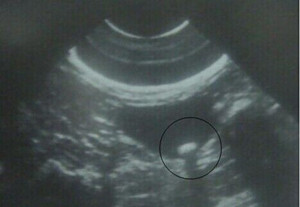

一、B型超声波检查:胆总管结石检查方法是什么呢?虽然价廉不开刀,对胆囊结石的准确率达98%,但因受十二指肠等空腔脏器的影响,对胆总管结石的准确率仅为0%左右,特别对十二指肠后段胆管难以显示,假阳性及假阴性率均较高。

三、CT扫描:CT对胆总管结石的诊断优于B超,准确率可达80%左右,但难以显示胆管系统病理改变和结石数量,大小,分布等状况,是较好的胆总管结石检查方法。